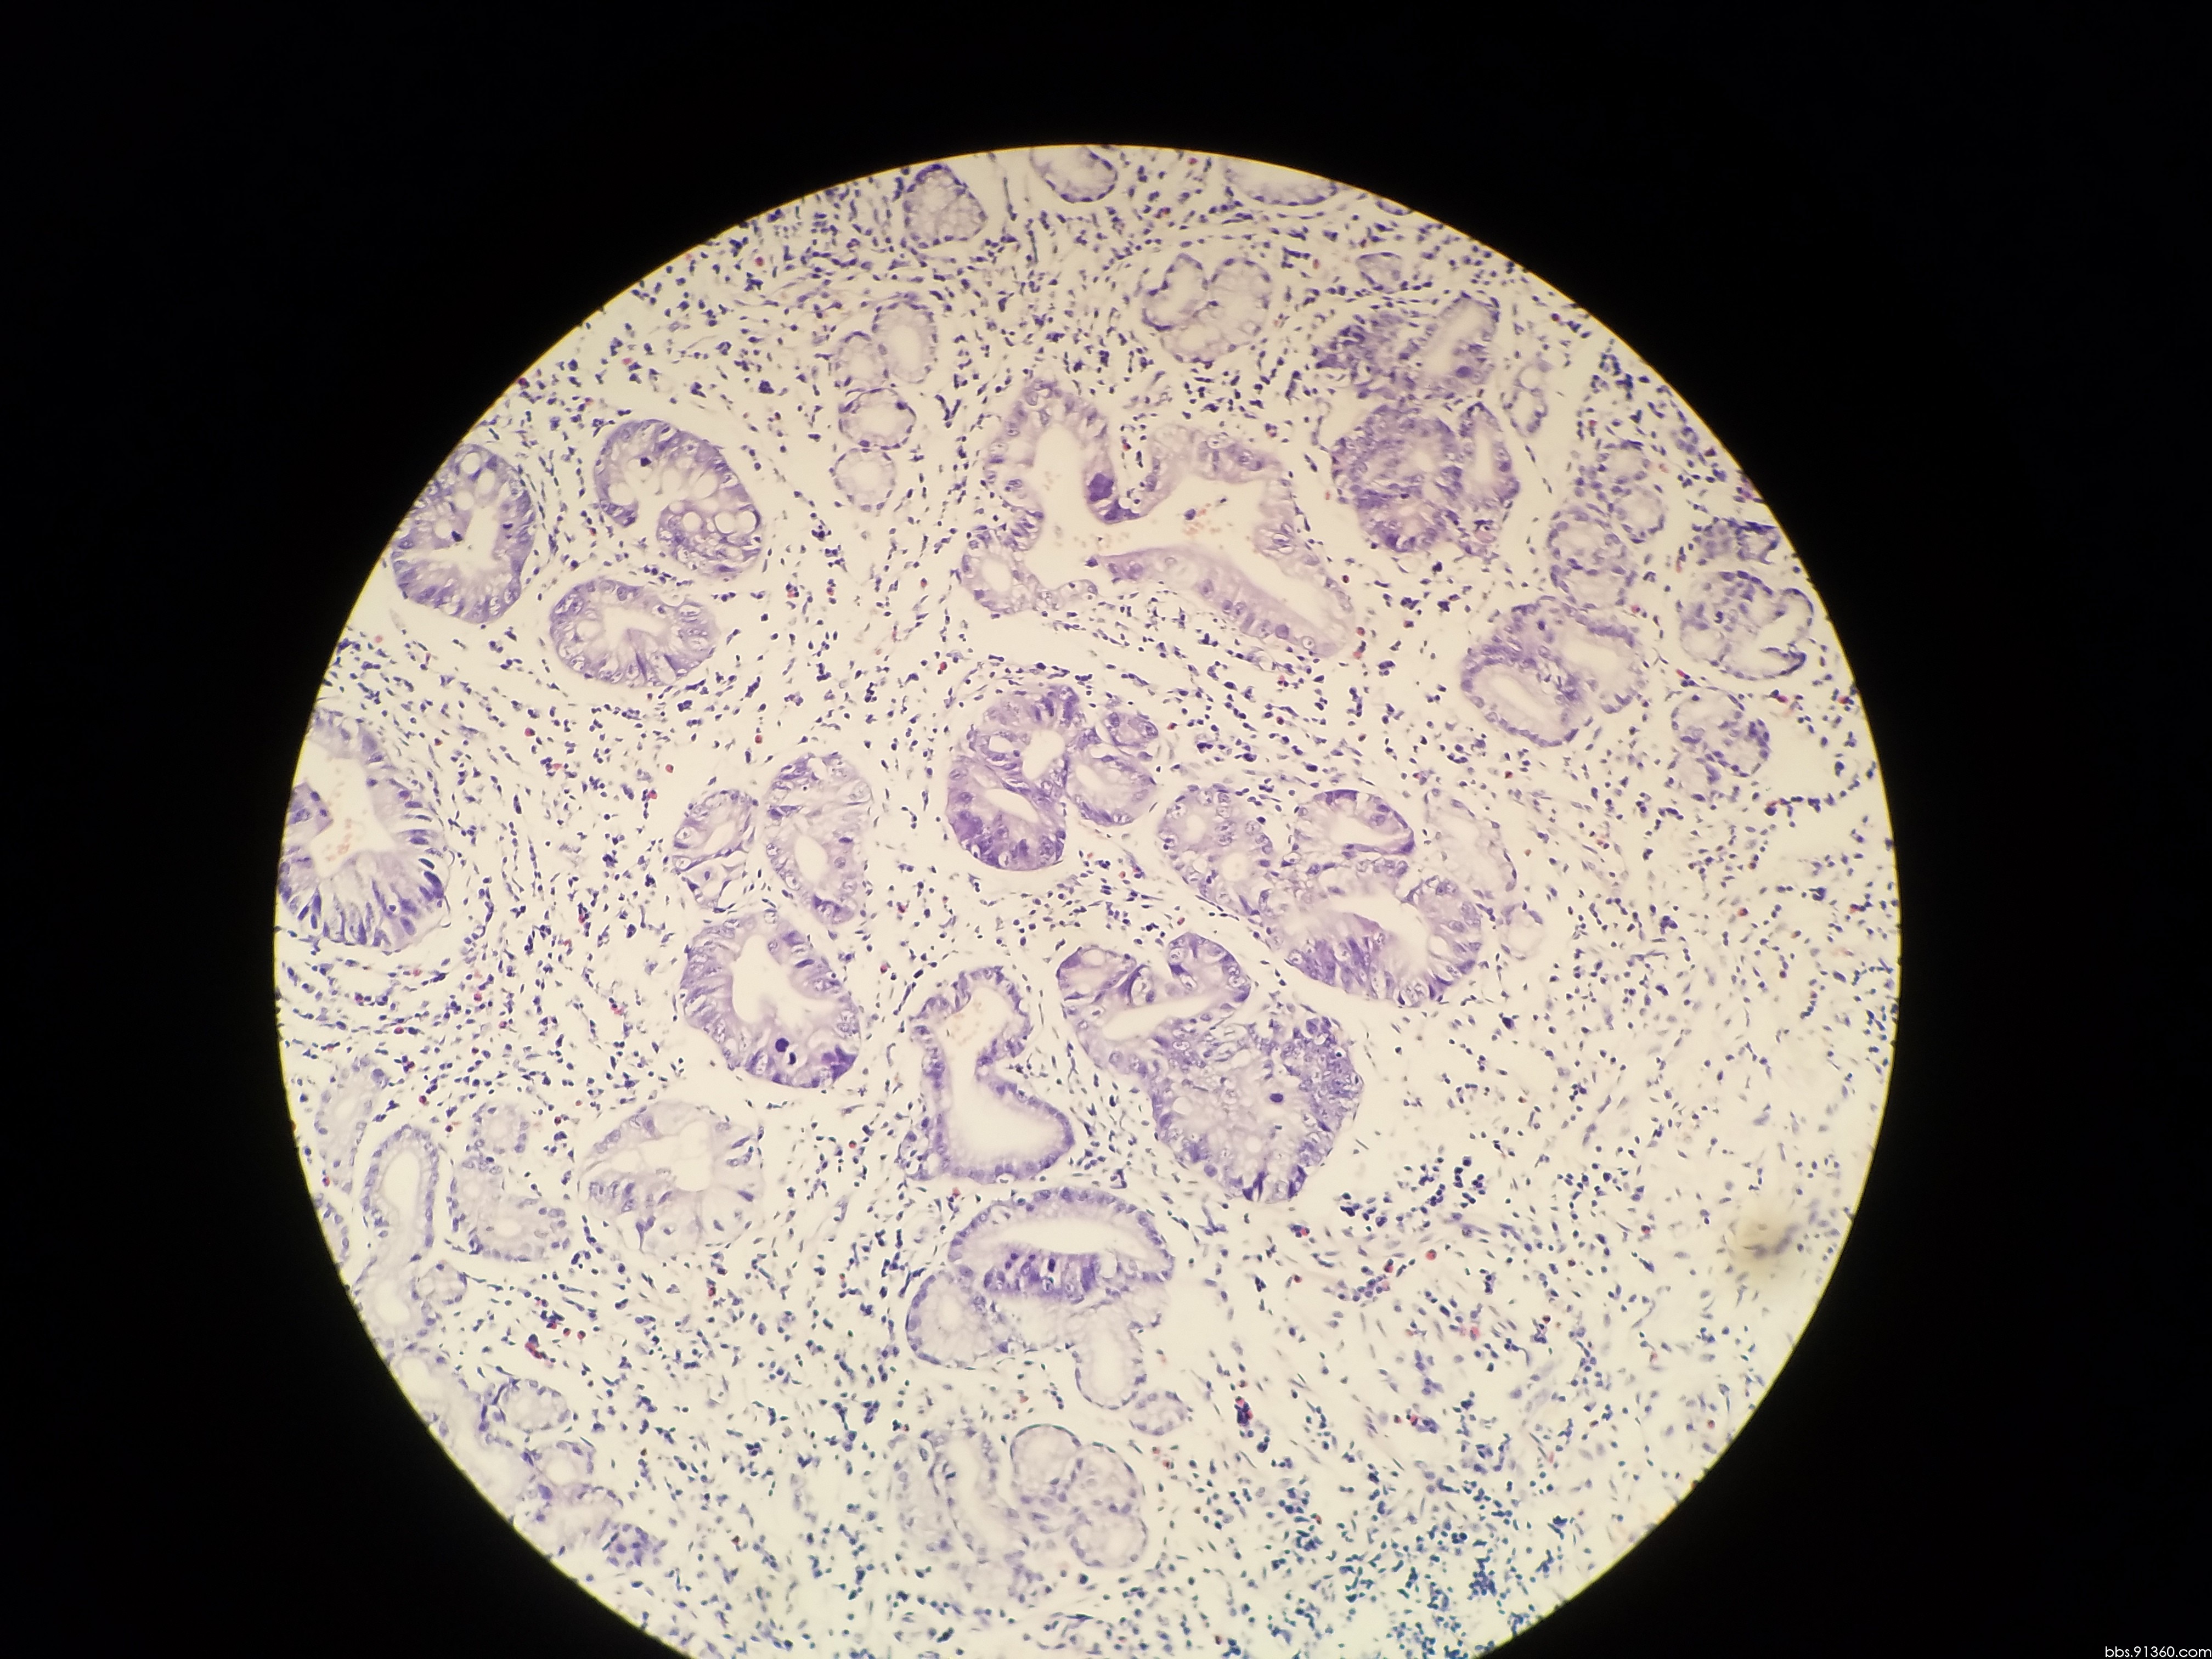

胃窦部黏膜组织活检镜下如图所示胃黏膜发生的有关病变的描述

胃窦部黏膜组织活检镜下如图所示胃黏膜发生的有关病变的描述错误的是

胃窦部黏膜活检

胃窦部黏膜活检

胃窦部黏膜活检

胃窦部黏膜活检